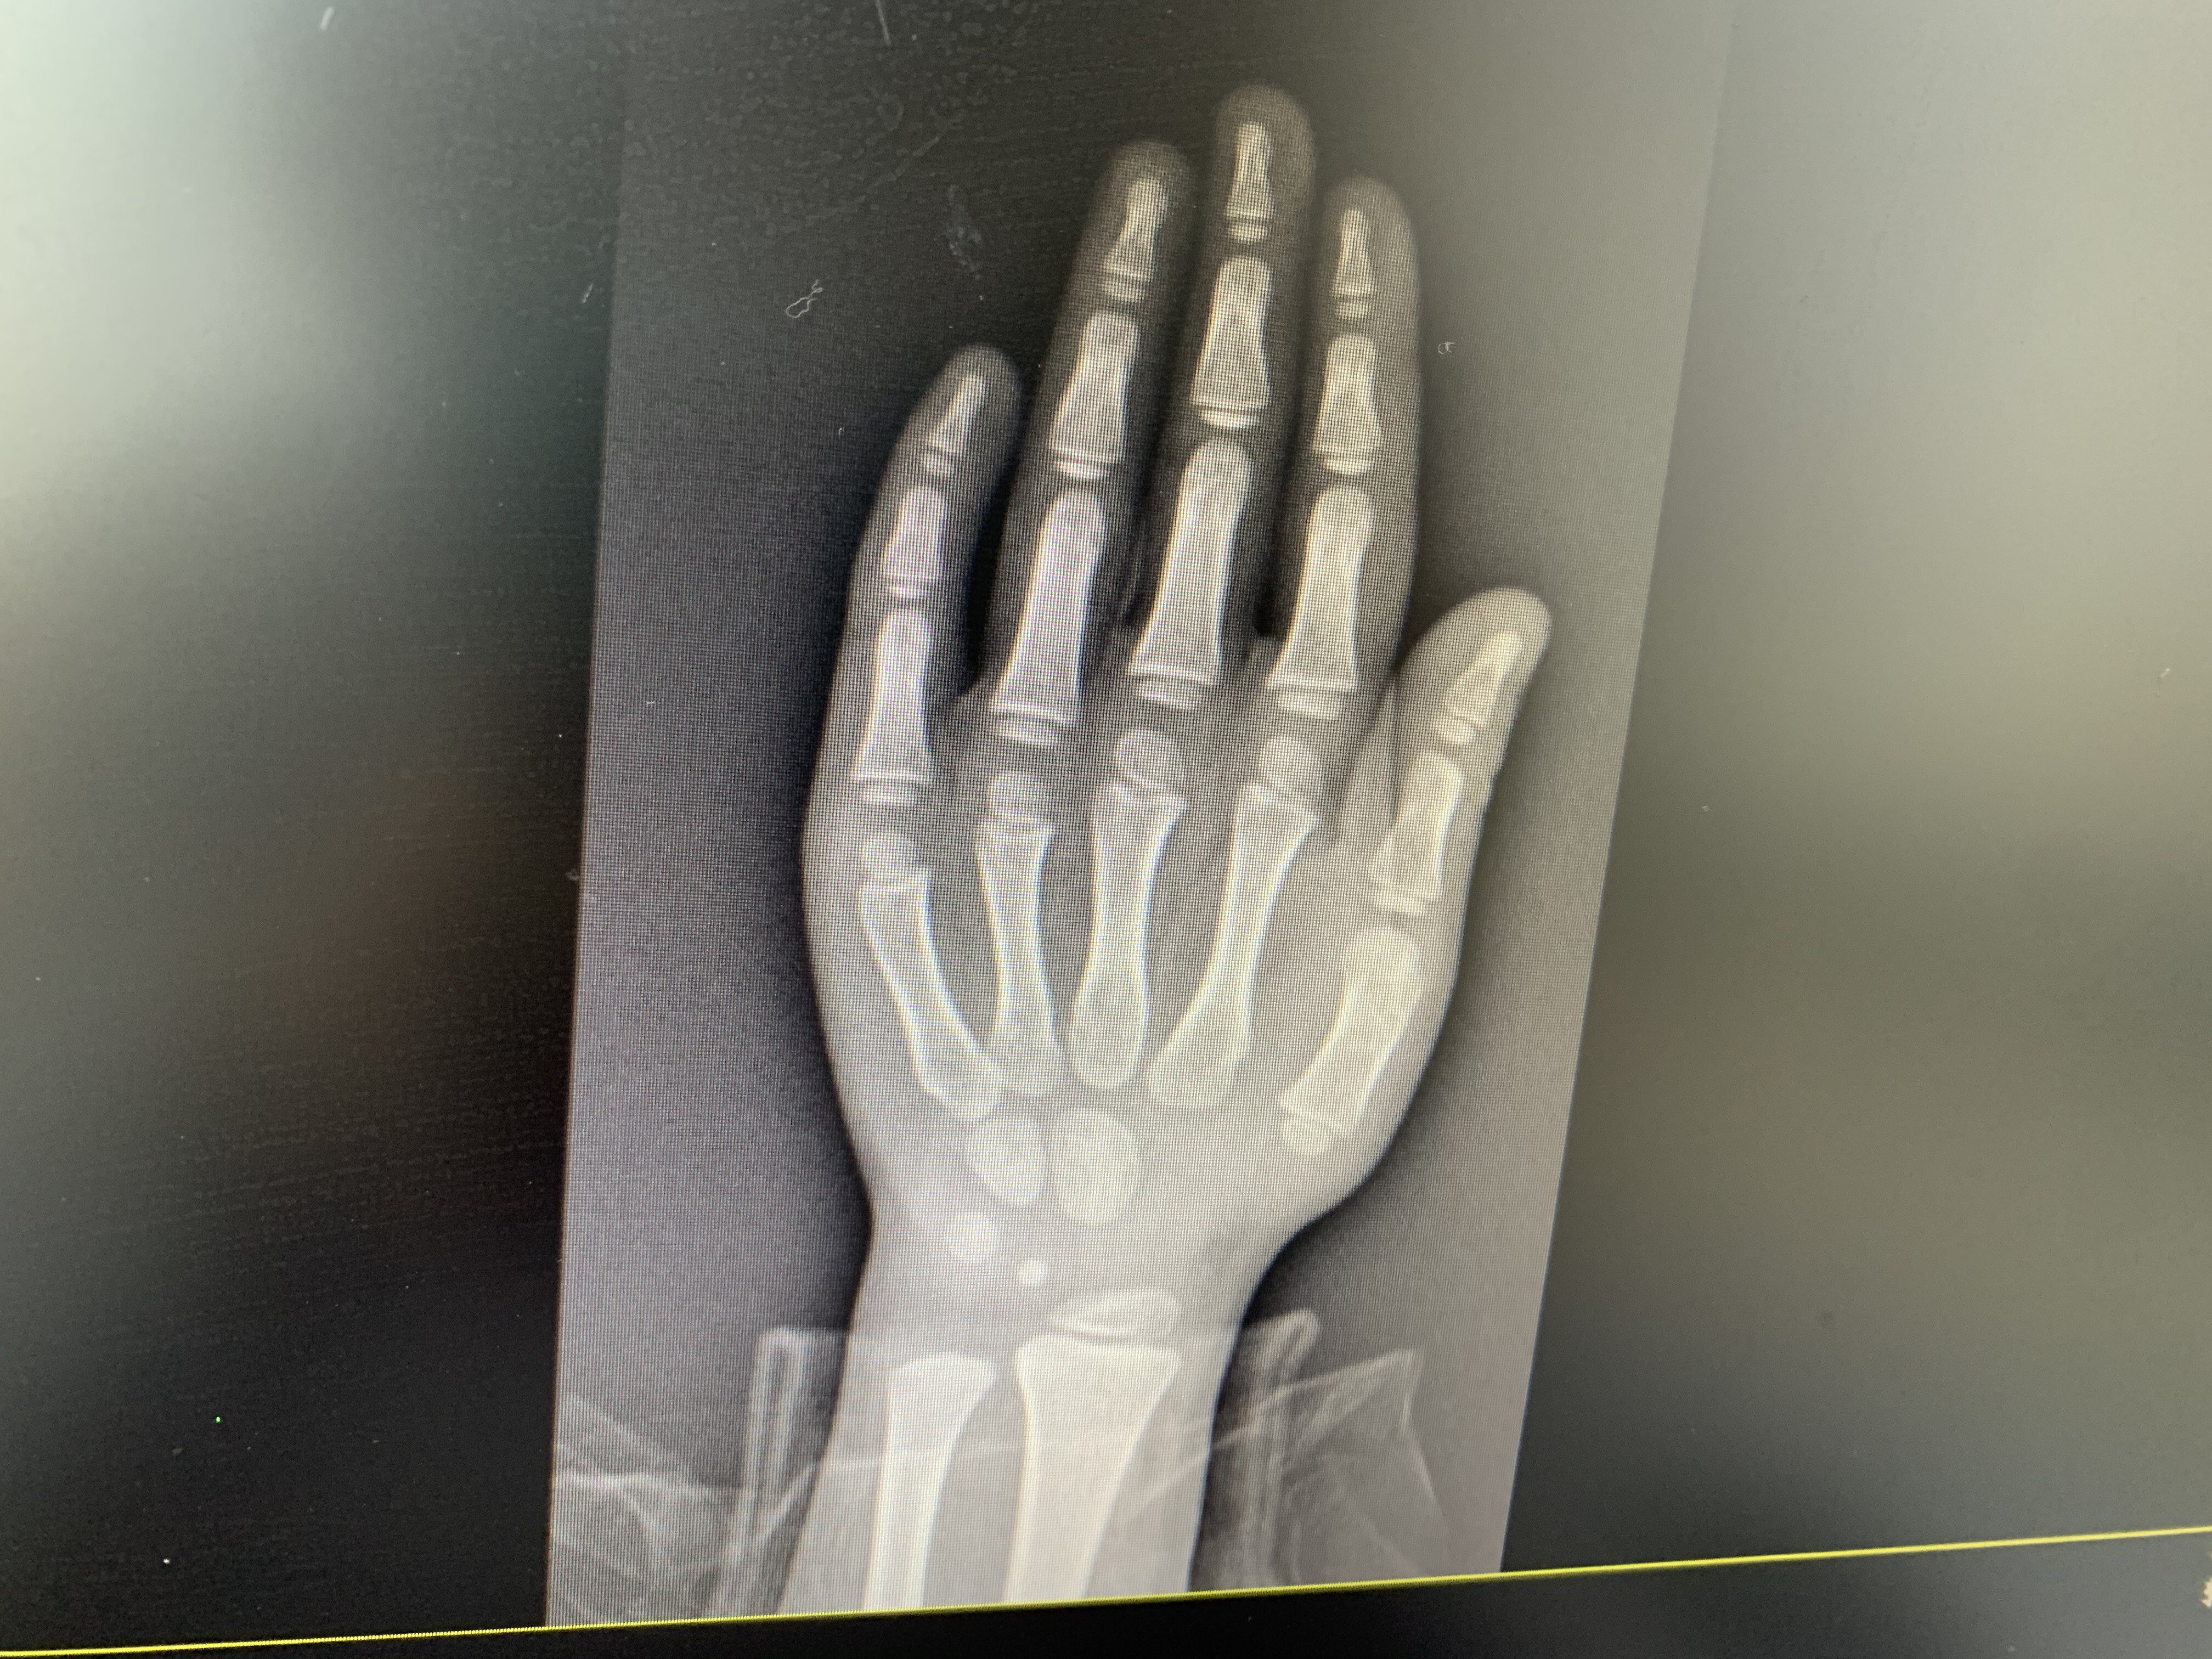

發(fā)表于2017.01.123520人已讀每年到了寒暑假期,各大醫(yī)院的兒童內(nèi)分泌門診總是人滿為患,絕大多數(shù)的小朋友和家長都是奔著一個目的來的——想長高。所以,今天我們就來談?wù)勆砀叩臒?。隨著各種偶像劇的上映,在很多家長心目中,男生180cm,女生165cm仿佛已經(jīng)成為了“標(biāo)配”,但理想很豐滿,現(xiàn)實往往卻很骨感。很多家長就會有疑問:為什么我們家寶貝就長不高呢?下面就給大家介紹下身材矮小的原因:1.生長激素缺乏:這也是目前小朋友身材矮小最常見的原因,而導(dǎo)致生長激素缺乏的原因又包括:先天性垂體發(fā)育不良、生長激素釋放激素缺陷、生長激素受體缺陷、胰島素樣生長因子I缺陷。通俗的講,就是導(dǎo)致身高增長的原材料不足。2.非內(nèi)分泌缺陷性矮身材:包括家族性矮身材、特發(fā)性矮身材(就是醫(yī)生所說的不明原因的矮?。?、青春期發(fā)育延遲、營養(yǎng)不良性矮身材。這里提到的幾種原因從字面上都比較好理解。3.顱腦損傷:圍產(chǎn)期損傷(臀圍分娩、缺血缺氧性腦病、顱內(nèi)出血等)、顱底骨折、放射性腦損傷、腦炎后遺癥等。這幾種原因一般都有明確的疾病史。4.腦浸潤病變:主要指的是各種腦部腫瘤5.其他:小于胎齡兒、精神心理性矮身材、染色體變異、骨骼發(fā)育障礙、慢性系統(tǒng)性疾病等。這里給大家解釋下,在我們臨床工作中,偶爾會碰到的一種疾病叫做特納綜合征(Turner’ssyndrome)就是一種典型的染色體變異,以女性患兒為主,少數(shù)男性患兒也會發(fā)生,主要表現(xiàn)為一條性染色體缺失或結(jié)構(gòu)異常,臨床表現(xiàn)主要是身材矮小,蹼狀頸、心理發(fā)育比正常兒童慢,需要完善染色體、生殖系統(tǒng)B超明確診斷。很多家長就會問:上面羅列出這么多病因,怎么才知道我們家小朋友屬于哪一種?來到兒童內(nèi)分泌門診,醫(yī)生首先會對小朋友進(jìn)行身高體重的測量,然后詢問出生史、疾病史、有無頭部外傷、平時飲食、睡眠情況、父母身高以及近期身高增長情況等。然后就會先做一個左手骨齡片檢查,部分年齡偏大的小朋友會加做一個左膝關(guān)節(jié)正側(cè)位片的檢查。有了骨齡片的檢查后,醫(yī)生心中就會對矮小原因有一個初步的判斷,有以下情況的小朋友,我們會做進(jìn)一步的檢查。①高低于正常參考值減2SD(或低于第3百分位數(shù))者;②骨齡低于實際年齡2歲以上者;③身高增長率在第25百分位數(shù)(按骨齡計)以下者,即:<2歲兒童為<7cm/年;4,5歲至青春期兒童<5cm/年,青春期兒童<6cm/年;④臨床有內(nèi)分泌紊亂癥狀或畸形綜合征表現(xiàn)者;⑤其他原因需進(jìn)行垂體功能檢查者。根據(jù)上面我們羅列的病因,醫(yī)生會開以下的檢查:生長激素激發(fā)試驗(部分患兒也使用生長激素運(yùn)動激發(fā)試驗替代),胰島素樣生長因子(IGF-1),甲狀腺功能,乙肝兩對半(乙肝的小朋友不能使用生長激素治療),肝腎功能心肌酶等生化檢測,染色體檢查,垂體磁共振等等。這些檢查的費(fèi)用大概2000-3000左右。檢查做完了,診斷也明確了,那么該如何治療呢?矮身材的兒童我們主張個性化治療,精神心理性、腎小管酸中毒等患兒在相關(guān)因素被消除后,其身高增長率即見增高,日常營養(yǎng)和睡眠的保障與正常的生長發(fā)育關(guān)系密切。而其他矮身材兒童在排除了乙肝病毒感染、顱內(nèi)腫瘤等疾病后,可以使用重組人生長激素治療。問答時間問:生長激素一般使用多久呢?答:我們建議有適應(yīng)癥的小朋友一般不宜短于1-2年。繼續(xù)用藥的指標(biāo)包括:1.療效是最首要的,使用生長激素有效的指標(biāo)是一年生長6cm以上,比較好的情況可以達(dá)到8-10cm,部分小朋友可以達(dá)到12cm左右;2.家庭經(jīng)濟(jì)條件,使用生長激素就好比整形美容,不屬于醫(yī)保范圍以內(nèi),因此在治療過程中,經(jīng)濟(jì)支持很重要。問:家長最關(guān)心的副作用怎樣呢?答:很多家長現(xiàn)在對激素有點談虎色變的感覺,其實家長心中的激素指的是醫(yī)學(xué)中的糖皮質(zhì)激素,主要應(yīng)用于過敏性疾病、免疫性疾病和部分腫瘤疾病,其主要副作用是出現(xiàn)向心性肥胖、痤瘡、鈣質(zhì)流失、股骨頭壞死等。而我們這里使用到的重組人生長激素不屬于糖皮質(zhì)激素,臨床應(yīng)用的副作用相對較小,主要可能存在:1.甲狀腺功能輕度減退;2.糖代謝異常,可能導(dǎo)致血糖輕度上升;3.注射部位紅腫、疼痛,通常在數(shù)日內(nèi)消失,可繼續(xù)使用,目前已甚少見。在我們臨床工作中,這些副作用還是比較少見,并且我們建議小朋友每三個月復(fù)診一次,出現(xiàn)副作用及時處理,基本也在可控范圍以內(nèi)。在這里祝各位小朋友健康快樂成長!各位家長朋友們有任何疑問,歡迎到我門診或者通過網(wǎng)上向我咨詢,我的門診地點是余姚市婦幼保健院(市二院),生長發(fā)育門診副高(兒童內(nèi)分泌??崎T診):每周一、六全天;普通號-生長發(fā)育門診:每周三全天(不顯示醫(yī)生名字)。預(yù)約方式:1、預(yù)約電話:0574-62909999,2、微信搜索“余姚市婦幼保健院”公眾號-發(fā)消息-互聯(lián)網(wǎng)醫(yī)院-立即預(yù)約。選擇兒童保健科-生長發(fā)育門診副高或者生長發(fā)育門診。